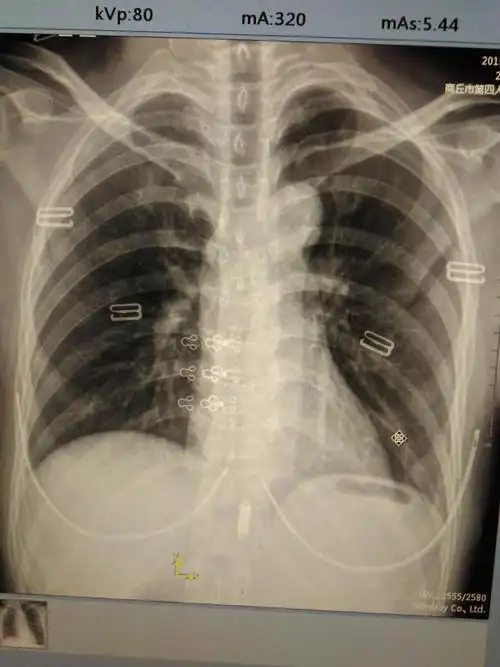

隐逸性肋骨骨折